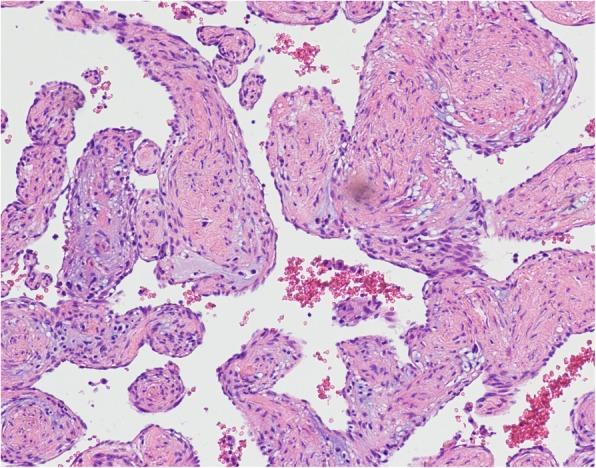

An asymptomatic 56-year-old woman was hospitalized due to a heart mass found by chest computed tomography (CT) during her annual physical examination. Coronary computed tomography angiography (CTA) disclosed a tumorous lesion, located in the left atrial roof and extended to the posterior wall of the aortic root and surrounding the left main coronary artery. However, there was no communicating branches between the hemangioma and coronary artery and no coronary artery stenosis. The tumor was excised with low-frequency electrocautery under cardiopulmonary bypass. The histopathological examination indicated the mass a cavernous hemangioma. The patient was discharged with an uneventful recovery.

一名56岁无症状女性因年度体检时胸部计算机断层扫描(CT)发现心脏肿物而住院。冠状动脉计算机断层扫描血管造影(CTA)显示一个肿瘤性病变,位于左心房顶部,延伸至主动脉根部后壁并包绕左冠状动脉主干。然而,血管瘤与冠状动脉之间无交通支,也无冠状动脉狭窄。在体外循环下用低频电灼切除肿瘤。组织病理学检查显示肿物为海绵状血管瘤。患者康复顺利出院。